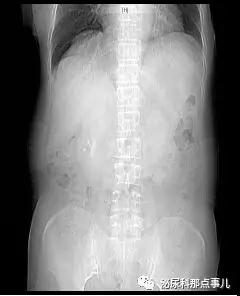

术前CT